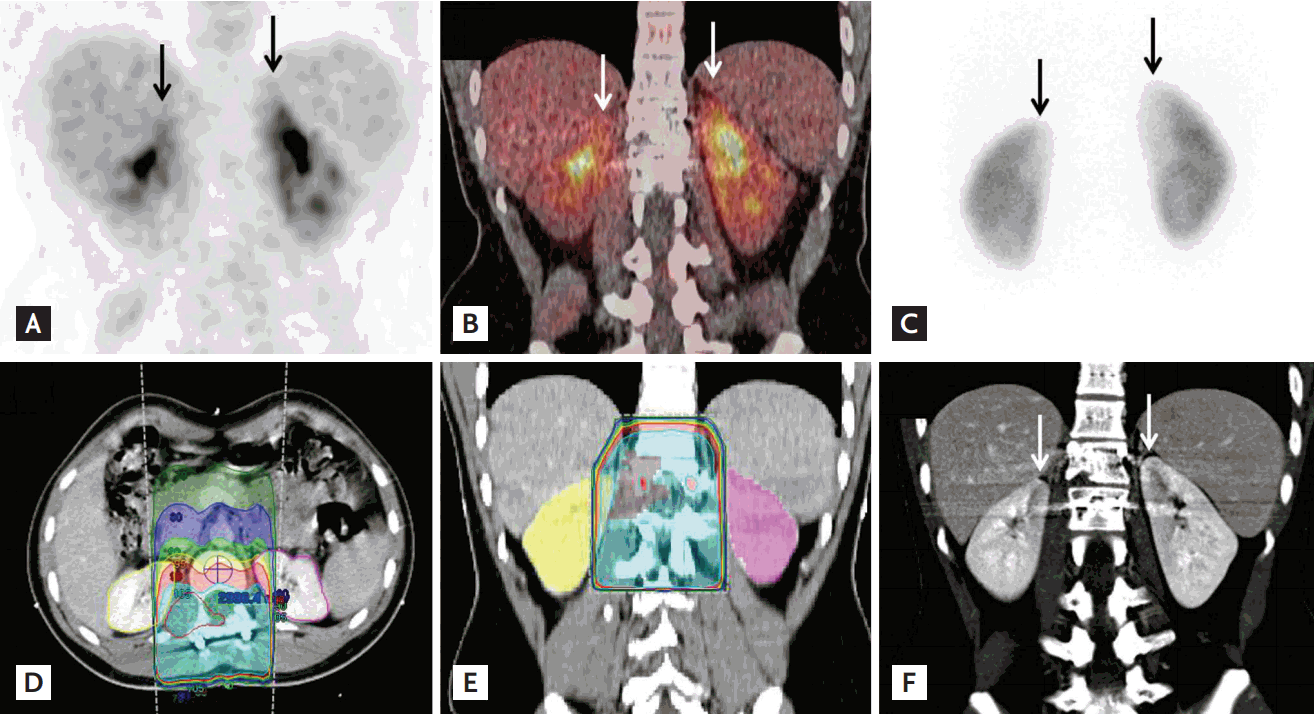

Figure 2.

On the same day with bone scan, fluorodeoxyglucose (FDG) positron emission tomography/computed tomography (PET/CT) was performed. (A, B) Mild longitudinal uptake was seen in the medial aspect of both kidneys on 18F-FDG PET/CT (arrows). (C) Five days later, 99mTc dimercaptosuccinic acid scan was performed to evaluate functional impairment, and photon defects were noted in the medial aspect of the renal cortices. Urea nitrogen and creatinine were within normal range (11.6 and 0.79 mg/dL). (D, E) These regions were included in the radiation field. Radiation therapy (RT) was delivered to the planning target volume at a dose of 30 Gy in 15 fractions using a three-dimensional RT technique followed by a boost of 20 Gy in 10 fractions using intensity-modulated radiotherapy, up to a total dose of 50 Gy in 25 fractions. (F) On contrast-enhanced abdominal CT, the medial aspects of both kidneys were a well-marginated, low density area.